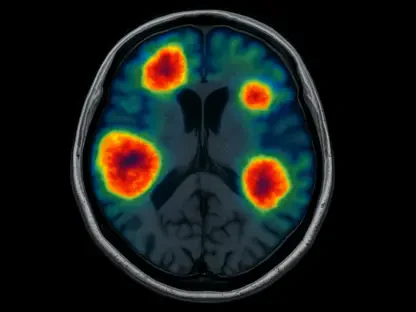

David Cameron’s decision to go public with his prostate cancer diagnosis underscores a pervasive issue: men’s reluctance to discuss or prioritize their health. After undergoing a prostate-specific antigen (PSA) test that revealed elevated levels, subsequent MRI scans and a biopsy confirmed the presence of cancer. He opted for focal therapy, a targeted approach using ultrasound to eliminate cancer cells in the affected area. Cameron openly acknowledged the cultural barriers that deter men from seeking help, emphasizing that many tend to delay or avoid medical check-ups altogether. His experience, spurred by familial encouragement and influenced by a fellow advocate’s story, reflects a broader need to normalize conversations about health challenges. By leveraging his platform, Cameron aims to inspire others to overcome hesitation and take proactive steps. His gratitude for early detection highlights how such actions can transform outcomes, offering a chance to address the disease before it advances to more critical stages. This narrative pushes for a shift in mindset, urging men to view health screenings as a vital and routine part of life.